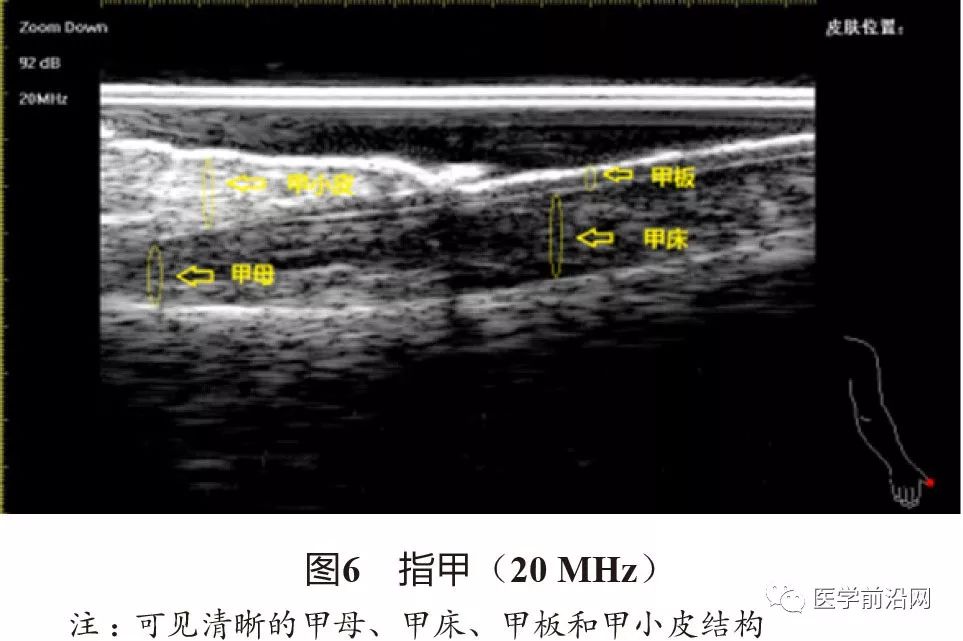

除皮肤层次外,部分皮肤附属器也可以在高频超声下清晰地观察到。在有终毛的区域(头皮、须毛、腋毛区),50~75 MHz超声可以观察到真皮内纵向平行排列的低回声条带(图5),对应毛囊结构。甲单位也可以在高频超声下很好地显示:甲板为两条纤细清晰的强回声带加中央的一条中低回声带,甲床为中等至低回声区域(图6)。在50~75 MHz超声下,甲板显示得更加清晰,而甲下常表现为声影(图7);在20~22 MHz超声下,甲床和甲母可以更完整地显示。